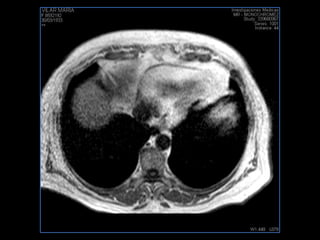

PROTOCOLO hígado graso AXIAL in phase y out phase AX T1 y AX fat sat +SAG T2  CON   GADOLINIO :  COR T1+AX T1(DIN) SAT: NO  FASE: RL THK: 4MM  COIL:  GAP: (FACTOR 1.4)  FOV: 40 CM NEX:2 SINCRONIZACION RESPIRATORIA EN 3 O 4 CICLOS ALE

PROTOCOLO hemocromatosis AXIAL supresión grasa /AX multieco en higado COR T2 AX T1 +SAG T2  CON   GADOLINIO :  COR T1+AX T1 SAT: NO  FASE: RL THK: 4MM  COIL:  GAP: (FACTOR 1.4) 1MM FOV: 40 CM NEX:2 SINCRONIZACION RESPIRATORIA EN 3 O 4 CICLOS ALE

resonancia de abdomen